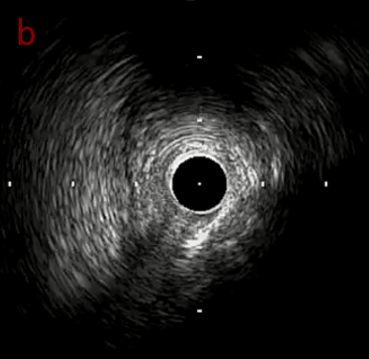

PreのIVUSではaの部位のみlipid plaqueを認め削ることでdistal embolismのリスクがあり、そのほかは270度の偏心性石灰化であるがwire biasは良好。

OAS low speedによる引きのsandingを3回行いIVUSを確認するとa-cでは心筋側側へのOASによる良好なbias変化と、それに伴いdの健常側への危険なbias変化を認めた。